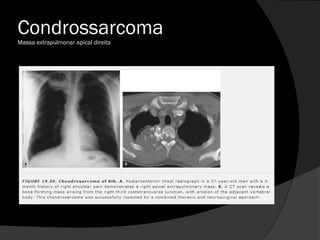

Condrossarcoma

Massa extrapulmonar apical direita